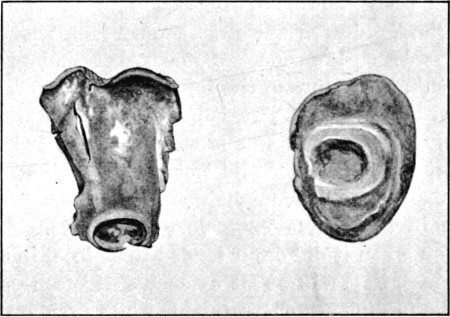

1. Section of Mauser Aperture of Entry To face p. 73

2. Section of Mauser Aperture of Exit 76

25a. Sections of Mauser Entry and Exit Wounds74